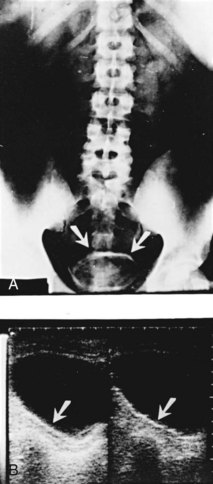

The majority of cases will show positive findings on excretory urography, the most common findings being hydrocalycosis, hydronephrosis, or hydroureter due to stricture formation (Wang et al, 2003). Early signs include the moth-eaten appearance of calyceal erosion and papillary irregularity. These signs are best seen on early excretory films, because they are often masked by increasing density of the contrast on later films of the IVU. Cavitary lesions communicating with the collecting system are characteristic of TB. These lesions eventually enlarge as parenchymal destruction ensues, and a picture similar to chronic pyelonephritis may be seen. Fibrotic distortion of the collecting system and ureter is also seen. Calyceal obliteration and amputation, hydrocalycosis, segmental or total hydronephrosis, and a shriveled reduced-capacity renal pelvis may all be signs of renal tuberculosis (Figs. 16-2 and 16-3). Scarring and angulation of the ureteropelvic junction (UPJ) may also occur, the so-called “Kerr’s kink” (Matos et al, 2005). Ultimately diminished or absent function and extensive calcification may be seen with autonephrectomy. If nonvisualized on IVU, the kidney is best evaluated by computed tomography (CT) or ultrasonography.

Tuberculosis of the ureter is commonly seen as a rigid, straightened “pipe-stem” ureter. A beaded, corkscrew appearance is sometimes also seen. Ureterovesical junction obstruction is caused by tuberculous cystitis or strictures of the distal third of the ureter (Fig. 16–4). Secondary stone formation on top of this stricture is an occasional finding. The cystogram films may show a small contracted bladder due to excessive fibrosis (Fig. 16–5). Of note, although IVU is being phased out by CT-urography in many developed countries (Stacul et al, 2008), IVU continues to be a reliable imaging modality for genitourinary TB in most parts of the world.